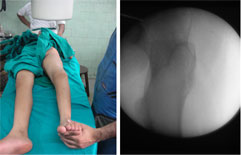

| These pictures were taken in the operating room for better understanding of the rotational deformity. The picture on the left was taken with the foot forward. The picture on the right shows the c-arm picture of the hip joint in the same position. The hip was in extreme internal rotation (normally this would have been in the mid-position, with both the lesser and greater trochanters visible). |

This picture on left shows that the knee has been bent to 90º and the hip has been externally rotated to the maximum extent possible.

The c-arm picture on the right was taken with the limb in the position as described above. The appearance of the hip joint is as would be in the frontal (antero-posterior) projection. The lesser trochanter is visible maximally and the greater trochanter is also seen without any overlap. |